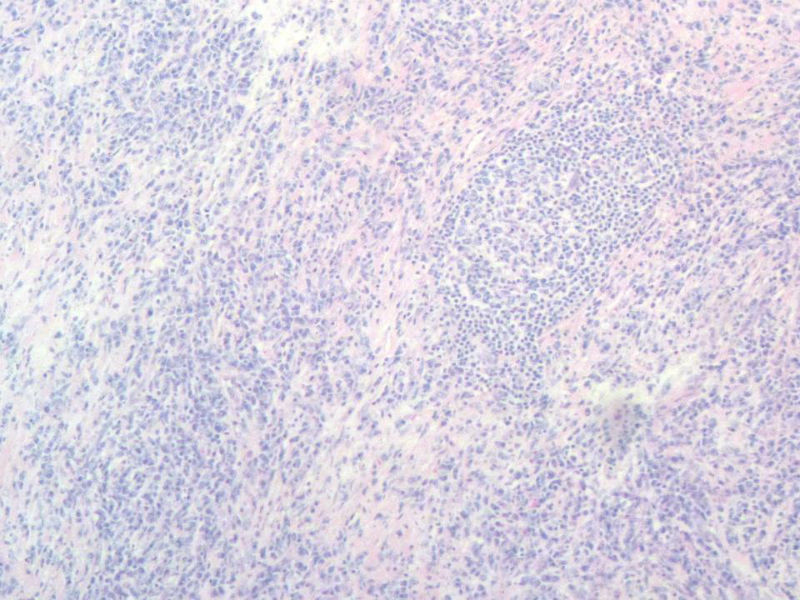

女,56岁,右颌下肿块两月余,检查肿块活动度差,手术切除。肉眼,灰白类圆形肿物,2X2X1厘米。包膜不完整,切面灰白色,质软。

与经治医生交流,患者目前一般状态良好,体表未触及肿块,CT各主要器官未见病变。结合免疫组化,我们考虑为浆细胞肉芽肿,但这个部位发生罕见,请指点!谢谢!

能产生显著淋巴滤泡的一些病变在很多专著甚至教科书中都有比较一致的描述。浆细胞肉芽肿的概念本身就有很多争议,WHO呼吸系统和软组织分册均将其归为炎性肌纤维母细胞瘤的同义词,似乎强调梭形细胞在其诊断中的意义。如果浆细胞肉芽肿是最合适的名称的话,那也是少见病例发生在少见部位并有不典型的形态学表现。

另外,网络读片不能完整地看到肿块的结构,肿块能否定是淋巴结吗?如果是淋巴结,我个人没有淋巴结浆细胞肉芽肿的读片经验,能不能考虑或排除一下浆细胞型的castleman或其它?